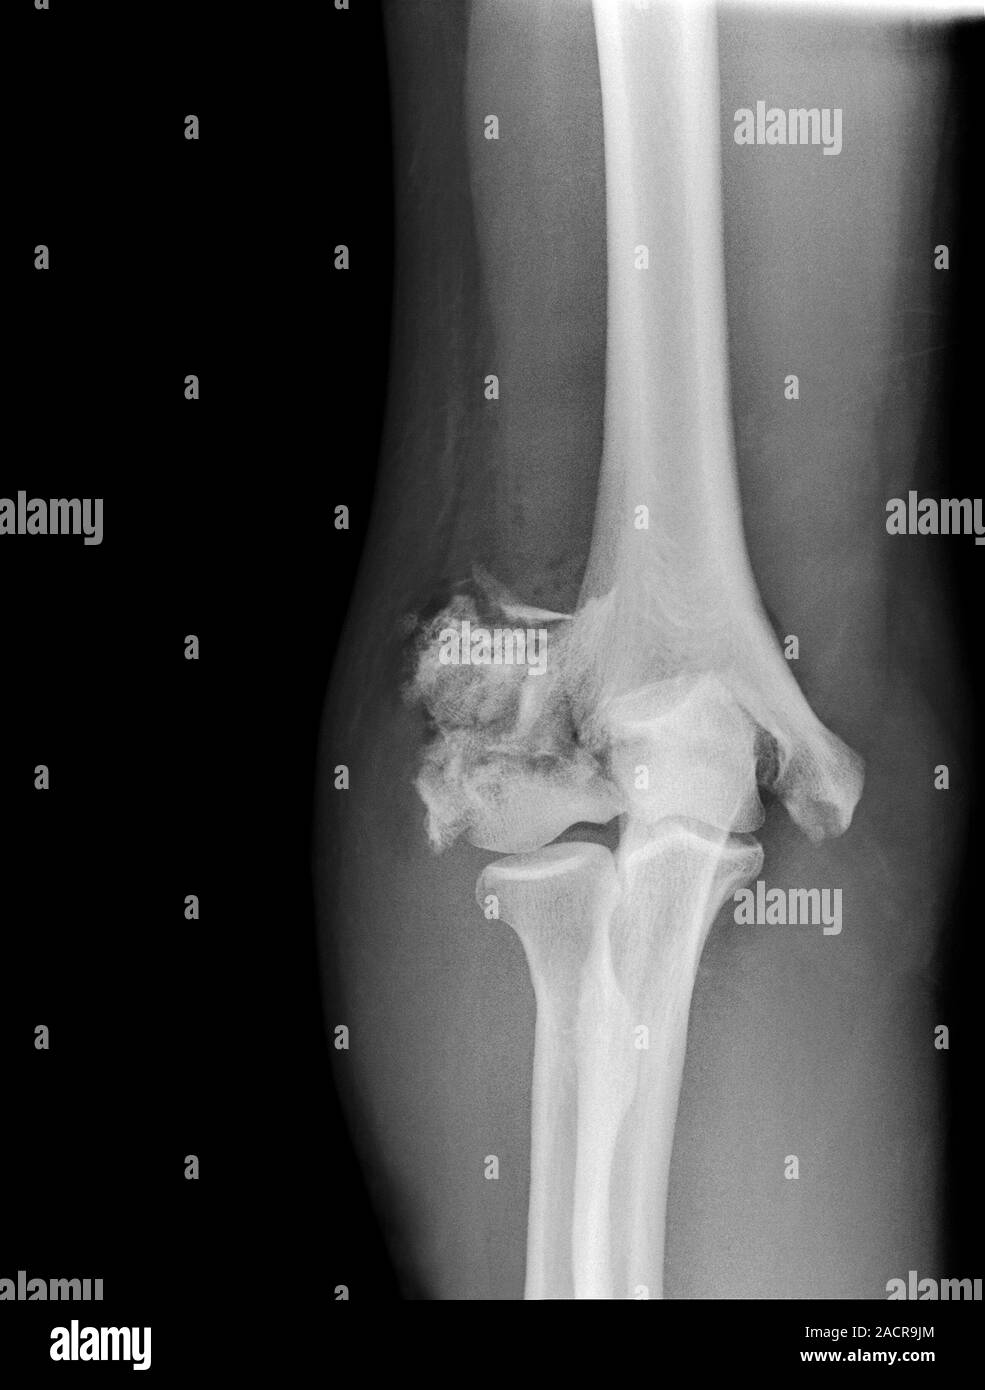

From www.alamy.com

Broken elbow. Xray of the arm of a 55 year old male patient with Broken Elbow Tips  Learn about the causes, symptoms, and treatment options for elbow fractures, which can range from minor to severe. Learn how physical therapy can help you recover from a broken elbow and prevent stiffness and weakness. Find out how to prevent infection, restore elbow motion, and avoid. Learn about the causes, symptoms, diagnosis, treatment, and recovery of a broken elbow, a. Broken Elbow Tips.